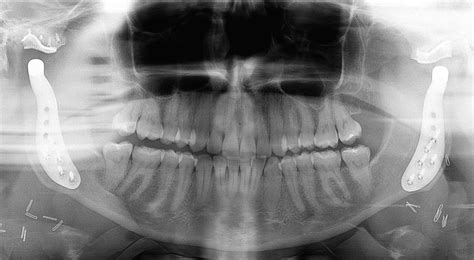

Diagnosing First Bite Syndrome can be challenging, as the symptoms are often transient and may not be present during a dental examination. However, a dentist or oral surgeon can typically make a diagnosis based on a thorough medical history and a physical examination of the jaw and teeth. In some cases, imaging tests such as X-rays or MRI scans may be ordered to rule out other potential causes of jaw pain.